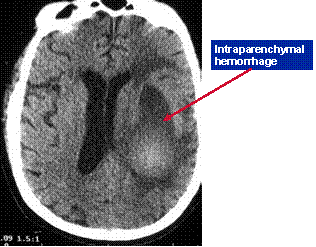

Traumatic intracranial hemorrhage

Intraparenchymal hemorrhage